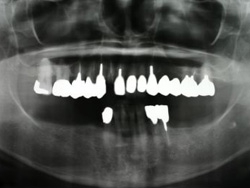

両側5歯症例

両側5歯症例両側5歯症例両側5歯症例 主訴-義歯のバネが壊れて手前の歯が痛んできた。 術前(旧義歯装着、鏡像) 術前(下顎粘膜面、鏡像)術前(下顎粘膜面、鏡像)術前(下顎粘膜面、鏡像) 術前レントゲン術前レントゲン術前レントゲン 術前口腔内(正面観)術前口腔内(正面観)術前口腔内(正面観)

術後(鏡像)術後(鏡像)術後(鏡像) 術後口腔内(正面観)術後口腔内(正面観)術後口腔内(正面観)もう入れ歯は要らなくなりました。 術後レントゲン術後レントゲン術後レントゲン